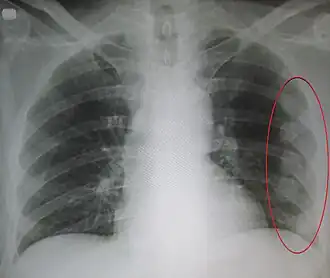

Рентгенограмма грудной клетки. Обозначена область множественных старых переломов рёбер.

Проводят рентгенографию грудной клетки. Однако при данном методе не всегда удаётся выявить перелом. Поэтому диагноз перелома рёбер обычно устанавливают на основании клинических данных (анамнез, жалобы, объективные данные). Для исключения осложнений проводят клинический анализ крови и мочи.